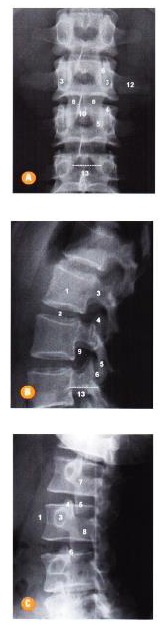

Com base nas seguintes radiografias da coluna lombar, assinale a alternativa com a adequada identificação das estruturas anatômicas.